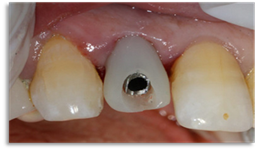

Endo-buccal examination (Figure 1) revealed the presence of the 22 roots.

Figure 1: Occlusal view of the maxilla showing the fractured crown of 22.